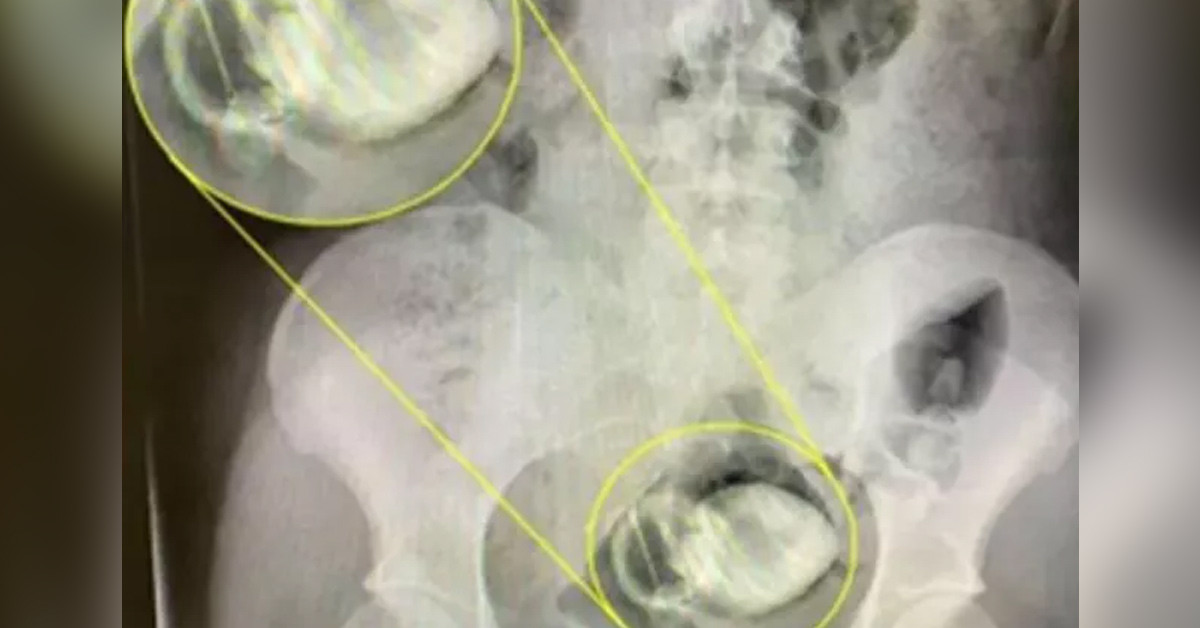

Hastanede yapılan operasyon sonrası oyuncak sıkıştığı yerden çıkarıldı. Sushine çıkartılan seks oyuncağını hatıra olarak saklamak istedi ve kargo ile erkek arkadaşına göndereceğini belirtti.

Kendi yöntemleri ile çözemeyen kadın mecbur ambulansı aradı ve operasyon geçirmek zorunda kaldı.